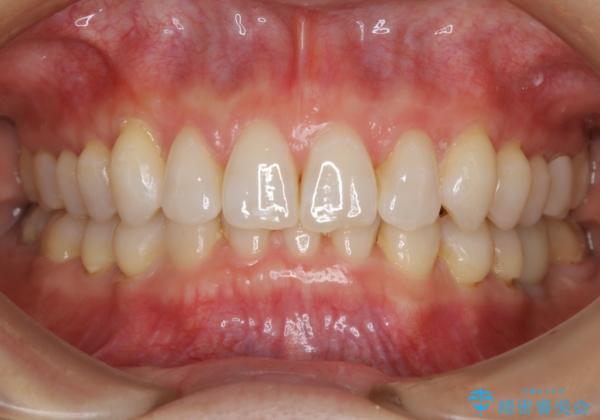

【抜歯】矯正治療とインプラントで正常な噛み合わせを実現

様々な治療プランを患者さんと相談させて頂き、最終的にインプラントで噛み合わせを回復させていくこととなり、まず悪くなっている歯を抜歯することから開始しました。